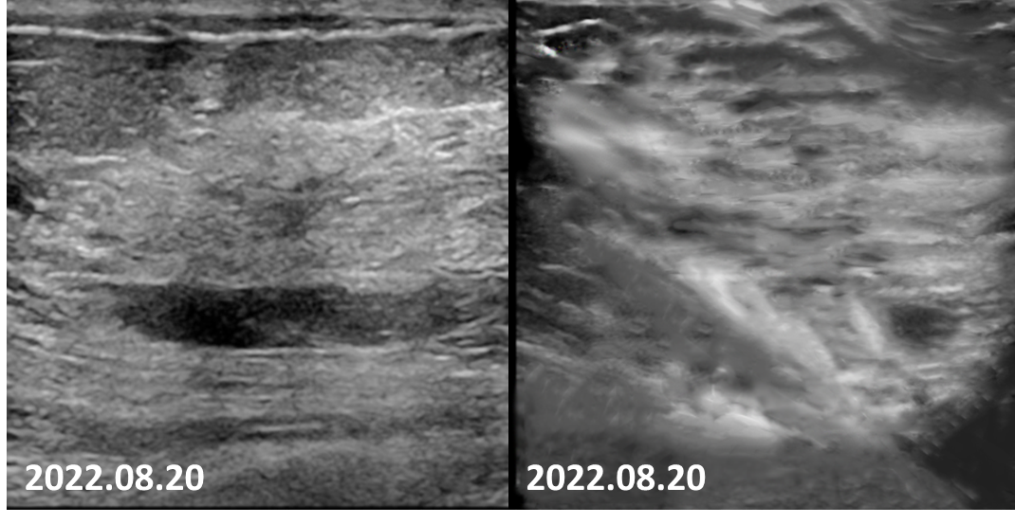

2022-05-21乳腺超声报告:左乳可见多处低回声结节,较大者位于12点钟,大小约47mm×27mm×35mm,距体表10mm,距乳头35mm,形态不规则,边缘成角,内回声不均匀。CDFI:内可及点状血流信号。左侧腋窝可见数个淋巴结回声,髓质消失,较大者大小约12mm×8mm,CDFI:内可见点状血流信号。右侧腋窝及双侧锁骨上窝未见明显肿大淋巴结。

图2.患者乳腺彩超可见肿瘤毛刺征明显,呈浸润性生长,腋窝淋巴结形态失常。

2022-08-20乳腺超声:左乳可见多处低回声结节,较大者位于12点钟,大小约11mm×7mm×11mm,距体表10mm,距乳头35mm,形态不规则,边缘成角,内回声不均匀。CDFI:内可及点状血流信号。左侧腋窝可见数个淋巴结回声,髓质消失,较大者大小约12mm×8mm。CDFI:内可见点状血流信号。右侧腋窝及双侧锁骨上窝未见明显肿大淋巴结。

图8 4疗程后,患者左乳肿物核心基本消失,淋巴结缩小至正常大小。